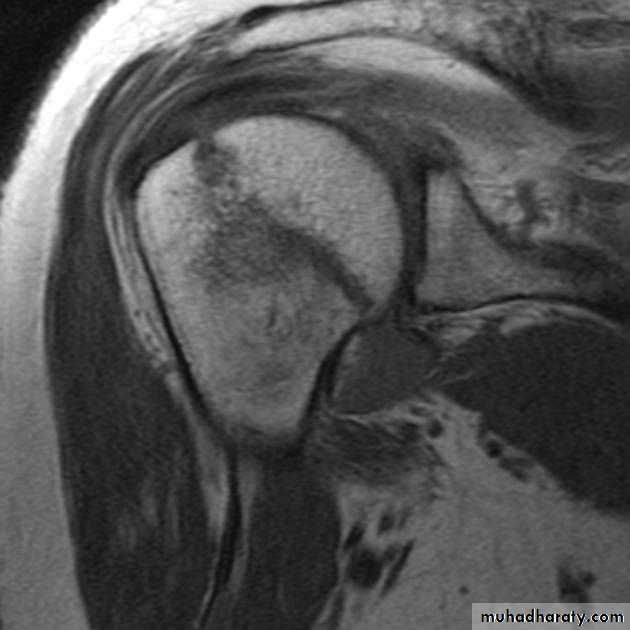

MRI

Conservative

12Treatment type one